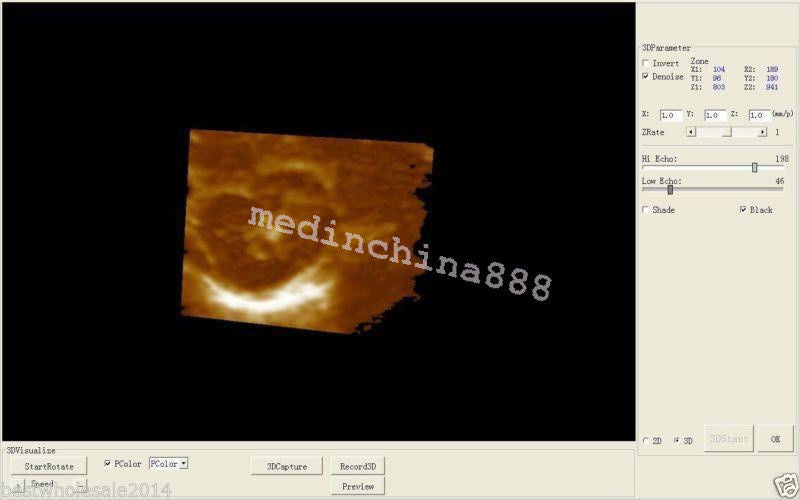

The Laptop LCD Digital 10.1-Inch Ultrasound Scanner is designed for high-quality imaging. This portable device offers detailed visuals, allowing healthcare professionals to deliver accurate diagnoses effortlessly. Equipped with both convex and transvaginal probes, it enhances versatility in various medical procedures. Its compact design ensures that you can carry it easily between locations, making it an essential tool for any medical practice. The user-friendly interface further simplifies operation, so you can focus on patient care without unnecessary distractions.